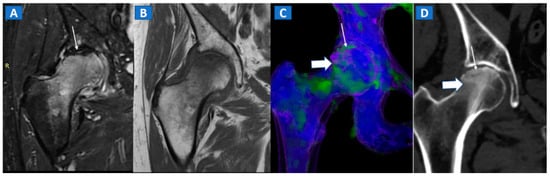

Figure 5.

A 58-year-old female with AVN of the right femoral head. On the coronal STIR MRI image (A), a hypointense serpiginous subchondral line, evident as a double line sign (arrow), is associated with diffuse BME involving the femoral neck and trochanteric region. On the corresponding T1-weighted image (B), hypointense BME seems to spare the medial aspect of the femoral head. On the DECT coronal 3D image (C), a flattened subchondral edematous area is depicted, with sclerosis-related artifacts hindering clear imaging of any BME of the head (thick arrow), although BME is apparent on the femoral neck. On the corresponding 1 mm coronal CT image with a soft-tissue window (D), it is possible to depict an increased density corresponding to the BME distribution (thick arrow), and a subtle subchondral hypodense line, which would be consistent with the diagnosis of a subchondral fracture (thin arrow). R = right.

The diagnosis of osteonecrosis, defined as the ischemic death of bone, is based on the presence of a double line sign, BME, and subchondral fractures at MRI. With standard high-resolution CT images available (Figure 5), DECT can been used to identify BME and associated imaging findings, as well as to reliably diagnose AVN of the femoral head [9]. Importantly, DECT images can reliably identify subchondral fractures and cortical bone involvement, which are key in the prognosis and management of AVN of the femoral head (Figure 5). Thanks to high resolution images, DECT could be used for staging AVN, depicting for example cystic and sclerotic radiographic changes in early phases, or BME around sub-chondral collapsed areas. CT is also a highly reliable imaging tool in evaluating articular narrowing and calcific loose bodies.